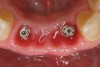

Preoperatively, 1 g of amoxicillin was administered. Using local anesthesia (lidocaine 1:100,000 epinephrine), extractions of teeth No. 23 to No. 26 were performed without raising a flap and with gentle luxation to preserve the remaining facial osseous plate. The sockets were curetted prior to implant placement. A vacuum-formed surgical guide, fabricated based on a diagnostic wax-up of the desired tooth positions for the subsequent fixed prosthesis, was used during implant placement. Osteotomies were performed at sites No. 23 and No. 26 and positioned toward the lingual aspects of the sockets (Figure 3A and Figure 3B). Two tapered implants (OsseoTite™ 313, BIOMET 3i™, Palm Beach Gardens, FL) measuring 3.25 mm x 13 mm were placed. Conical prosthetic abutments (3-mm height) were used to facilitate joining the two implants in a screw-retained fixed partial denture (Figure 4). A laboratory-processed acrylic-resin provisional restoration was altered to allow connection to the temporary cylinders. The provisional was placed into the vacuum-formed surgical guide that was now used to maintain the provisional in the correct 3-dimensional position (Figure 5) while being attached to the temporary cylinders with acrylic resin intraorally. Once a sufficient amount of acrylic resin was placed to secure the cylinders to the provisional, it was removed from the mouth and its contours were completed at the laboratory bench (Figure 6A). The two central incisor sockets were grafted with small-particle allograft material (Puros® Allograft, Zimmer Dental, Carlsbad, CA) to maintain gingival architecture beneath two ovate pontics (Figure 6B). The provisional restoration was inserted and the screws tightened to 20 Nt-cm of torque.

The patient was given postoperative instructions and advised to maintain a soft diet for 6 to 8 weeks to protect the implants. The patient was followed weekly for the first 3 weeks and monthly thereafter. After 4 months of healing, the provisional restoration was removed and the soft tissues were examined. Mature, keratinized gingival tissues were present facially, lingually, and interproximally. Nonkeratinized tissue could be seen at the tissue surfaces of the ovate pontics and in the intrasulcular regions of the implant abutment units. No clinical probing depths beyond 1 mm were found adjacent to the abutments. The healed tissue represented an acceptable clinical result especially in light of the gap that had been present at the time of implant placement (Figure 7A and Figure 7B). Final impressions were made, and the permanent ceramo-metal screw-retained prosthesis was placed within 8 weeks (Figure 8).